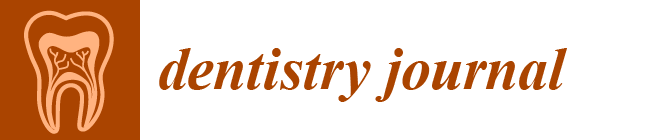

2. Materials and Methods

2.2. Materials and Methods

4.4. Periodontal and Radiologic Parameters